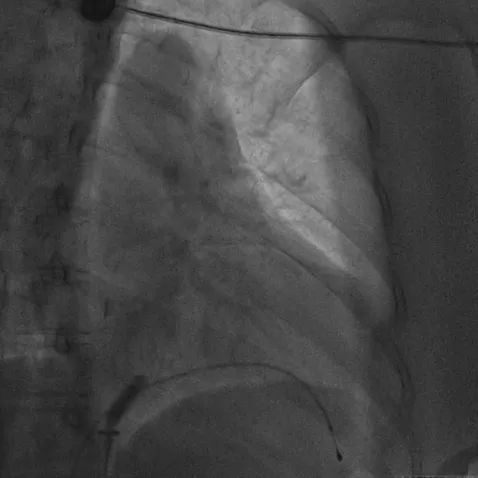

无导线起搏器被抓捕、拔除的术中影像

治疗团队经过充分讨论并评估了手术风险及预后,与家属反复沟通,决定为张女士实施无导线起搏器移除+生理性起搏+心脏再同步除颤器(LOT-CRTD)植入术。术前,汤宝鹏教授带领治疗团队进行了详细的文献查阅和充分的病情评估,对术中可能出现的各种风险做好了应急预案。术中,手术团队使用圈套器成功抓捕无导线起搏器Micra尾端并顺利拔除,同时给患者植入左束支心脏再同步起搏除颤器。手术顺利,患者术后恢复良好。